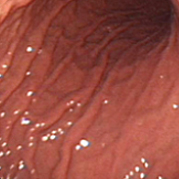

정상적인 위